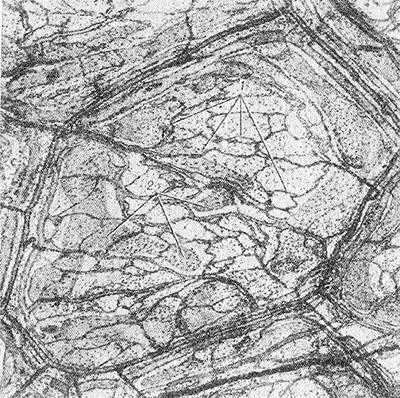

Рис. 4. Электронограмма элементов стенки кровеносных капилляров: а — внутримозговой капилляр (1 — гликопротеидовое покрытие, 2 — эндотелиоцит); х 60 000; б — межклеточный контакт в эндотелиальной оболочке гломерулярного капилляра почки (1 — цитоплазма соседних эндотелиоцитов, 2 — контактирующие цитолеммы, 3 - межмембранный промежуток); х 90 000; в и г — гломерулярные капилляры почки (1 - открытые фенестры; 2 — диафрагмальные фенестры в цитоплазме эндотелиоцитов); X 70 000; д — стенка синусоидного капилляра печени (1 — прерывистый контакт между смежными эндотелиоцитами 2); х 35 000.

Как показали электронно-микроскопические наблюдения, стенка кровеносного К., часто называемая капиллярной мембраной, состоит из двух оболочек: внутренней — эндотелиальной и наружной — базальной. Схематическое изображение строения стенки кровеносного К. представлено на рисунке 2, более детальное — на рисунках 3 и 4.

Эндотелиальная оболочка образована уплощенными клетками — эндотелиоцитами (см. Эндотелий). Число эндотелиоцитов, ограничивающих просвет К., обычно не превышает 2—4. Ширина эндотелиоцита колеблется от 8 до 19 мкм и длина — от 10 до 22 мкм. В каждом эндотелиоците выделяют три зоны: периферическую, зону органелл, ядросодержащую зону. Толщина этих зон и их роль в обменных процессах различны. Половину объема эндотелиоцита занимают ядро и органеллы — пластинчатый комплекс (комплекс Гольджи), митохондрии, зернистая и незернистая сеть, свободные рибосомы и полисомы. Органеллы сконцентрированы вокруг ядра, вместе с к-рым составляют трофический центр клетки. Периферическая зона эндотелиоцитов выполняет в основном обменные функции. В цитоплазме этой зоны располагаются многочисленные микропиноцитозные везикулы и фенестры (рис. 3 и 4). Последние представляют собой субмикроскопические (50—65 нм) отверстия, которые пронизывают цитоплазму эндотелиоцитов и бывают перекрыты истонченной диафрагмой (рис. 4, в, г), являющейся дериватом клеточной мембраны. Микропиноцитозные везикулы и фенестры, участвующие в трансэндотелиальном переносе макромолекул из крови в ткани и обратно, в физиологии называют крупными «норами». Каждый эндотелиоцит покрыт снаружи тончайшим слоем продуцируемых им гликопротеидов (рис. 4, а), последние играют немаловажную роль в поддержании постоянства микросреды, окружающей клетки эндотелия, и в адсорбции веществ, транспортируемых через них. В эндотелиальной оболочке соседние клетки объединяются с помощью межклеточных контактов (рис. 4, б), состоящих из цитолемм смежных эндотелиоцитов и межмембранных промежутков, заполненных гликопротеидами. Эти промежутки в физиологии чаще всего отождествляют с мелкими «порами», через которые проникают вода, ионы и белки с низким молекулярным весом. Пропускная способность межэндотелиальных промежутков различна, что объясняется особенностями их строения. Так, в зависимости от толщины интерцеллюлярной щели различают межэндотелиальные контакты плотного, щелевого и прерывистого типов. В плотных контактах интерцеллюлярная щель на значительном протяжении полностью облитерирована благодаря слиянию цитолемм смежных эндотелиоцитов. В щелевых контактах величина наименьшего расстояния между мембранами соседних клеток колеблется между 4 и 6 нм. В прерывистых контактах толщина межмембранных промежутков достигает 200 нм и более. Межклеточные контакты последнего типа в физиологической литературе также отождествляют с крупными «порами».